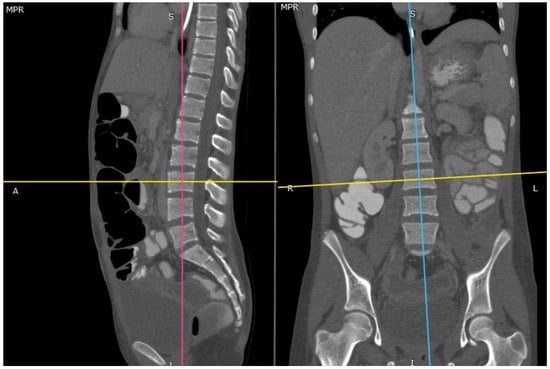

2.2. CT-Scan Analysis